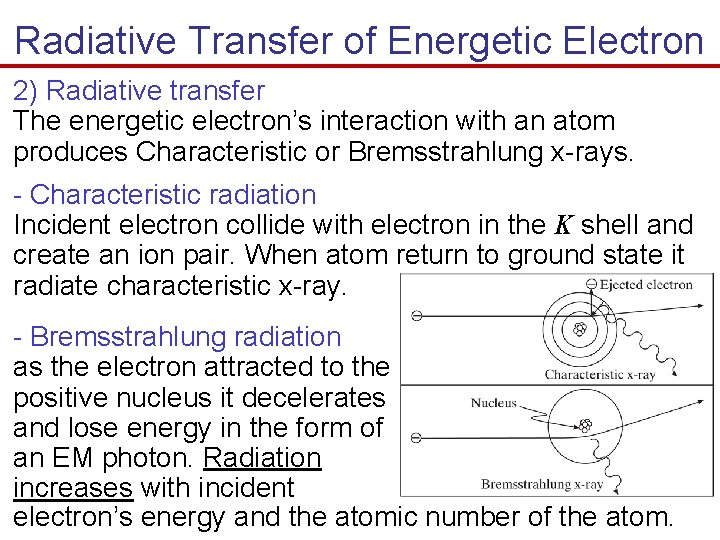

Radiative Transfer of Energetic Electron 2) Radiative transfer The energetic electron’s interaction with an atom produces Characteristic or Bremsstrahlung x-rays. - Characteristic radiation Incident electron collide with electron in the K shell and create an ion pair. When atom return to ground state it radiate characteristic x-ray. - Bremsstrahlung radiation as the electron attracted to the positive nucleus it decelerates and lose energy in the form of an EM photon. Radiation increases with incident electron’s energy and the atomic number of the atom.